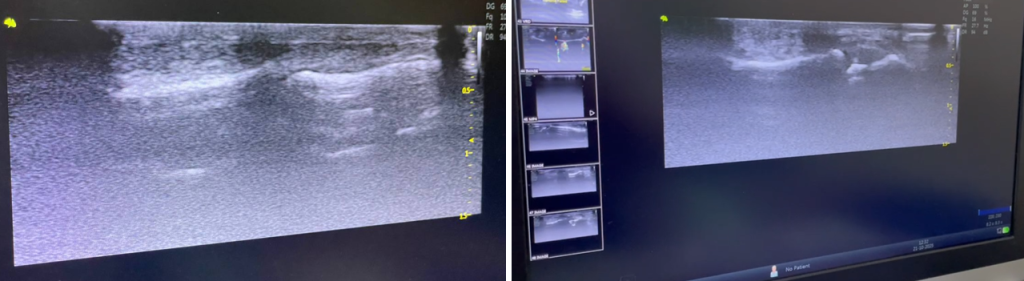

Наступний етап – ультразвукова діагностика.

УЗД з використанням високочастотних датчиків з частотою 14-15-16 МГц і більше дозволяє візуалізувати ділянку (кріплення) ентеза сухожилка до дистальної фаланги, та виявити ймовірний відрив кортикального фрагмента.

Проведення функціональних проб під час УЗД — візуалізує діастаз культі сухожилка (зміщення) від місця кріплення.

Пошкодження дистального ентеза сухожилка довгого розгинача 2 пальця. УЗД.